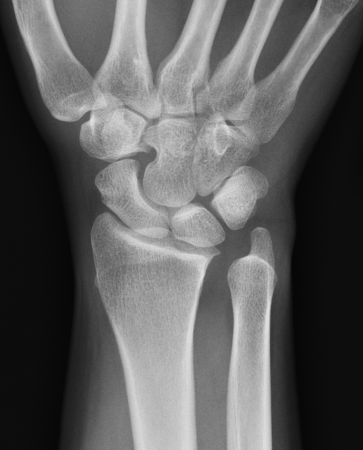

Isolated ulna styloid fractures with DRUJ instability

Classification ulna styloid process fractures

| Type 1: Tip fracture | Type 2: Base fracture |

|---|---|

|

Stable DRUJ

DRUJ potentially unstable |

Ulna styloid process fracture and acute DRUJ instability

Ulna styloid fracture with TFCC injury